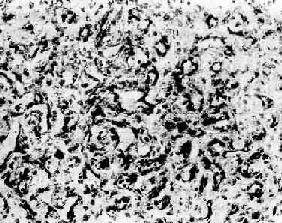

图7-15 纤维

组织由分化良好的纤维细胞构成,呈编织状排列,有丰富的胶原纤维

1.纤维(fibroma)组织内的胶原纤维排成束状,互相编织,纤维间含有细长的纤维细胞(图7-15)。外观呈结节状,与周围组织分界明显,有包膜。切面灰白色,可见编织状的条纹,质地韧硬,常见于四肢及躯干的皮下。此生长缓慢,手术摘除后不再复发。